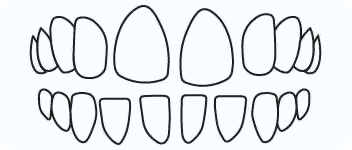

Cross Bite

In a crossbite, one or more of your lower teeth overlap the outer surface of your upper teeth. Crossbites can occur in front or back teeth.

Open Bite

In open bite there is no vertical overlap between teeth and open space exists between upper and lower teeth when jaws are closed.